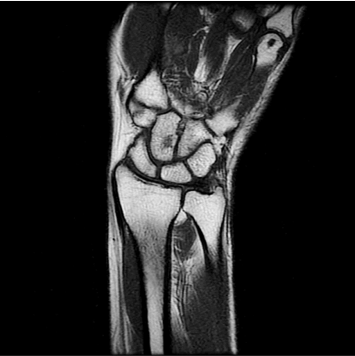

1:29 min촬영속도의 혁신, IAI

기존

IAI

IAI는 AI Deep learning을 통해 기존 장비의 촬영 프로토콜을 최적화합니다.

기존 프로토콜 대비 촬영 시간을 50% 단축시키며, 이미지 퀄리티는 증가합니다.